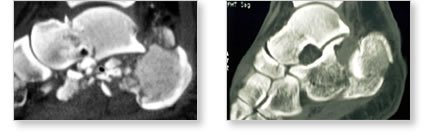

Diagnosing a heel fracture

Your doctor will try to pinpoint the area of pain and tenderness. You will probably need to get several x-rays of the heel and ankle area. A computed tomography (CT) scan may also be helpful. If you are also experiencing back pain, your doctor will recommend x-rays of the lower back as well to see if there is a fracture there.

The nerves that bring sensation and movement to the foot pass close to the heel bone. Your doctor will check their functioning to ensure that there is no damage. He or she will also make sure that an adequate supply blood is flowing to the toes and that pressure is not building in the muscles of the foot (compartment syndrome).